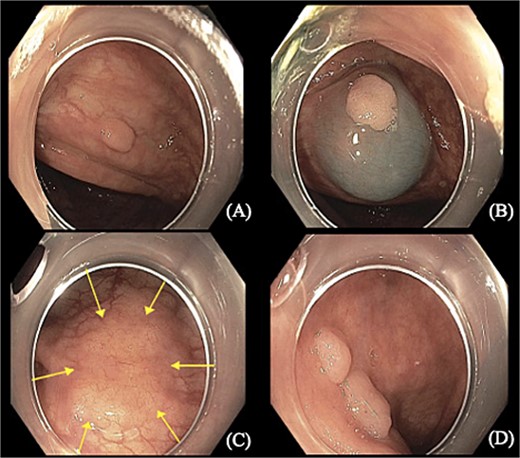

A 75-year-old female with a past medical history of hypothyroidism underwent her first screening colonoscopy. Colonoscopy showed a flat irregular polyp near the splenic flexure of the colon measuring 20 × 40 mm (Fig. 1). The polyp was resected, and biopsy results were consistent with FL grade I. Immunostaining demonstrated positivity to CD20, BCL-2, CD10, and CD21. Ki-67 staining demonstrated a low proliferation index (10%–20%) in lymphoma cells, with a high proliferation index (>90%) in the residual reactive germinal centers (Fig. 2). The lymphoma cells were negative for CD5 and cyclin 1 (Table 1). Other polyps were found in the proximal transverse colon and rectum, and pathology showed sessile serrated adenomas. Subsequently, the patient underwent PET/CT scan in order to estimate further lymphoma involvement. PET/CT scan revealed no evidence of FL nor increased colonic uptake (Fig. 3).

Colonoscopy images show (A, B, and D) sessile polyps found in the proximal transverse colon and rectum. (C) Flat irregular polyp near the colonic splenic flexure measuring 20 × 40 mm.